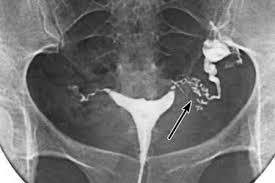

Проходимость маточных труб выявляется рентгенологическим обследованием, лапаротомией или гистеросальпингографией.